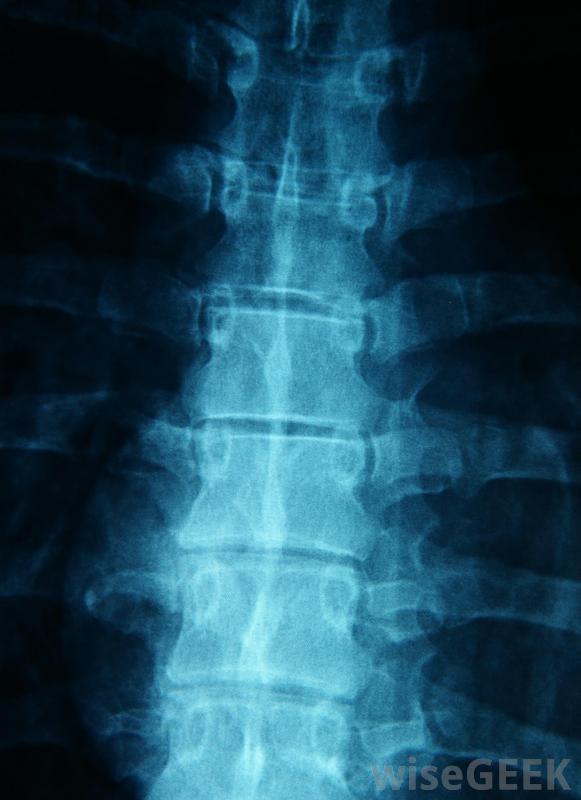

脊柱的X射线成像可能有助于找到慢性坐骨神经痛的根本原因慢性坐骨神经痛是多种多样的。许多人有持续的放射状疼痛,从他们的下背部通过臀部的一侧一直延伸到他们的一条腿。刺痛、麻木和肌肉无力是常见的感觉,它们可能会在整个腿部或坐骨神经的特定部位感觉到。对大多数人来说,慢性坐骨神经痛只是轻微的不舒服,他们仍然可以管理日常活动,如步行和开车。然而,有些人会经历衰弱的疼痛和虚弱,这大大限制了他们的活动水平和生活质量理疗有助于减轻坐骨神经的压力医生通常可以在体检时对慢性坐骨神经痛做出一个非常基本的诊断。医生可以询问症状,测试反应,并在腿部和臀部四处摸索,以找到疼痛的部位。为了找出根本原因,医生可能会要求对下脊椎进行x光和磁共振成像扫描椎间盘滑脱和磨损的迹象。慢性坐骨神经痛的治疗目标是纠正神经痛的主要原因。